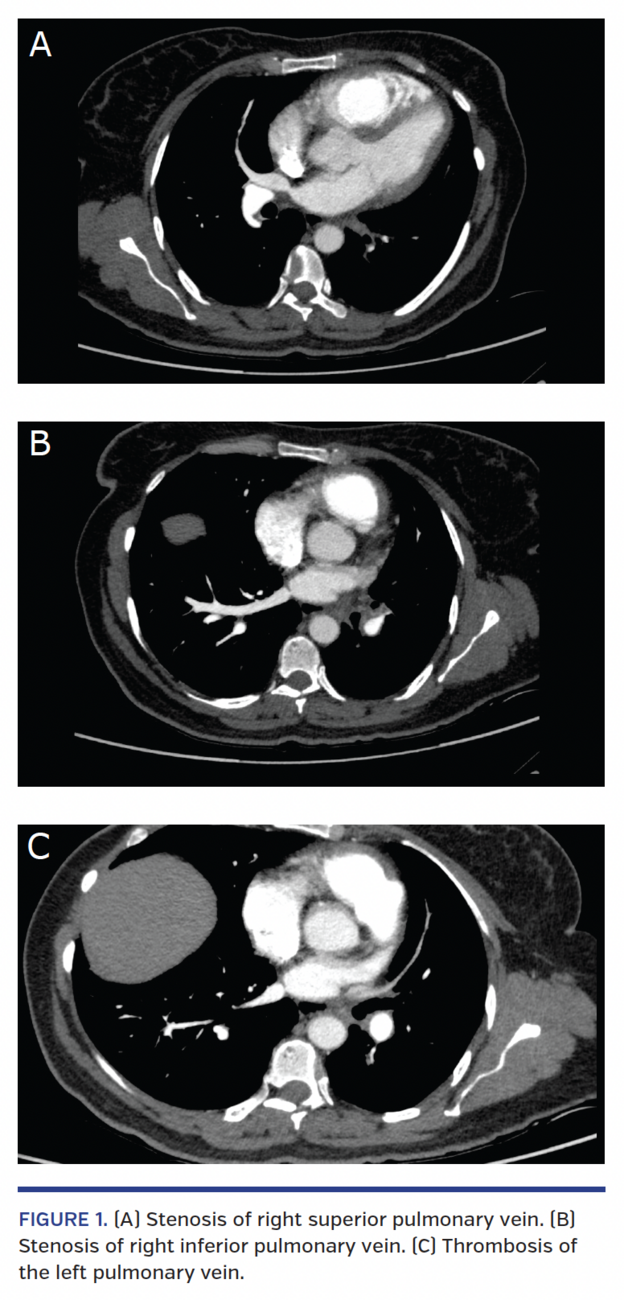

Angiographic computed tomography was performed (Figure 1), revealing severe stenosis of the four pulmonary veins, right ventricular dilation and suggesting total thrombosis of the left superior (LSPV) and left inferior (LIPV) pulmonary veins.